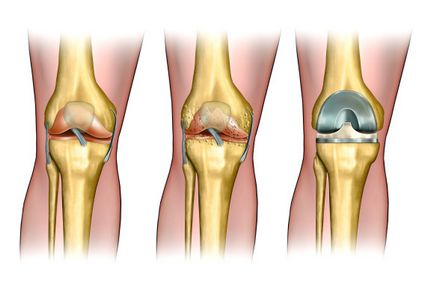

Бувають випадки, коли лікування безсило. Тоді проводять заміну власного суглоба на штучний протез. Така процедура називається ендопротезування.

Ендопротезування суглоба проводять в складних випадках захворювання